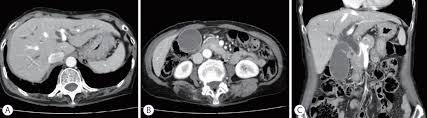

Comparison Of Double Layer Large Diameter And Conventional Small Diameter Plastic Stents For Preoperative Biliary Drainage In Resectable Distal Malignant Biliary Obstruction Scientific Reports - Advanix™ pancreatic stent device placement using naviflex™ rx delivery system.

Comparison Of Double Layer Large Diameter And Conventional Small Diameter Plastic Stents For Preoperative Biliary Drainage In Resectable Distal Malignant Biliary Obstruction Scientific Reports - Alibaba.com offers 1,732 biliary stent products.